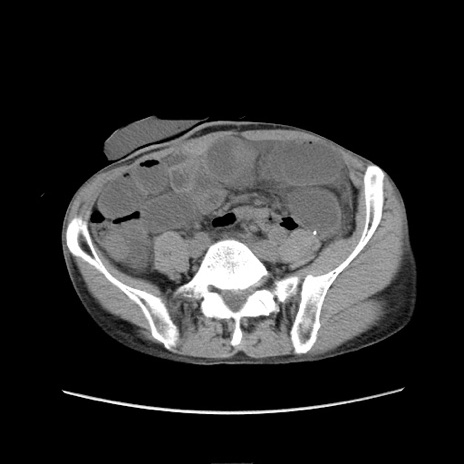

症例11(横断像)

【症例】 60歳代男性

【主訴】 下腹部痛

【現病歴】 本日夜中より下腹部痛の症状認め、受診。

【既往歴】 膀胱癌(膀胱全摘+尿管皮膚瘻術) 、胃癌術後

【身体所見】 BT 35.3℃、PR 58/min、BP 136/98mHg、腹部平坦、軟、腸蠕動音±、ストマ留置あり、左上腹部~正中部に圧痛あり、反跳痛なし。

【データ】WBC 5100、CRP0.01